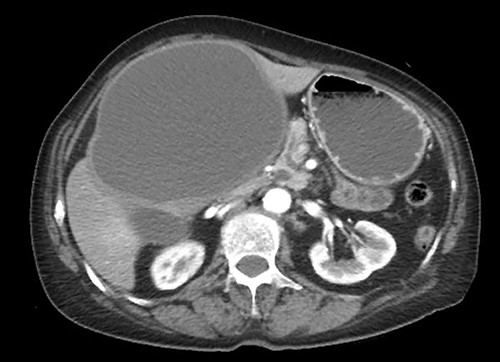

The hepatic cyst compressed the stomach, duodenum, pancreas and gallbladder, and the descending part of the duodenum was difficult to identify because of severe thinning caused by the compression. On magnetic resonance imaging, the giant cyst showed low signal intensity on T1-weighted and high signal intensity on T2-weighted images, and there was a solid component with a high signal on diffusion-weighted images on the dorsal side of the cyst (Fig. 2).

Giant cyst showed high signal intensity on T2-weighted images and fuller component in dorsal side showed high signal on diffusion-weighted images.